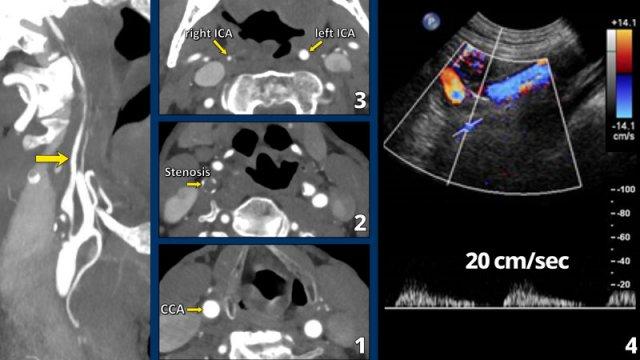

Gần tắc hoàn toàn (2)

Trong trường hợp này, động mạch cảnh chung có đường kính bình thường (hình 1).

Có hẹp nặng với mảng xơ vữa vôi hóa một phần tại vị trí xoang cảnh (2).

ICA ở đoạn trên vị trí hẹp có khẩu kính nhỏ (3). Xem thêm mũi tên trên ảnh tái tạo mặt phẳng đứng dọc.

Các tiêu chí chẩn đoán gần tắc hoàn toàn bao gồm:

- Khẩu kính ICA đoạn xa nhỏ hơn so với ICA bên đối diện (hình 3).

- Khẩu kính ICA đoạn xa nhỏ hơn so với động mạch cảnh ngoài (ECA) cùng bên (hình 3).

Vận tốc đỉnh tâm thu trên siêu âm Doppler thường tăng tương ứng với mức độ hẹp, tuy nhiên trong trường hợp gần tắc hoàn toàn, vận tốc đỉnh tâm thu sẽ giảm xuống mức rất thấp như trong trường hợp này (20 cm/giây).

Tiếp tục xem các ảnh mặt phẳng đứng dọc…

Lưu ý mảng vôi hóa tại vị trí xoang cảnh và khẩu kính nhỏ của ICA đoạn xa, nhỏ hơn so với khẩu kính của ECA.